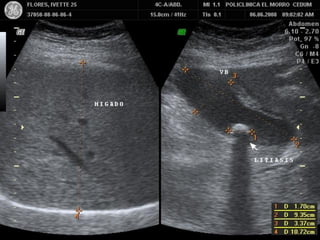

PATOLOGIA BILIAR

LITIASIS VESICULAR